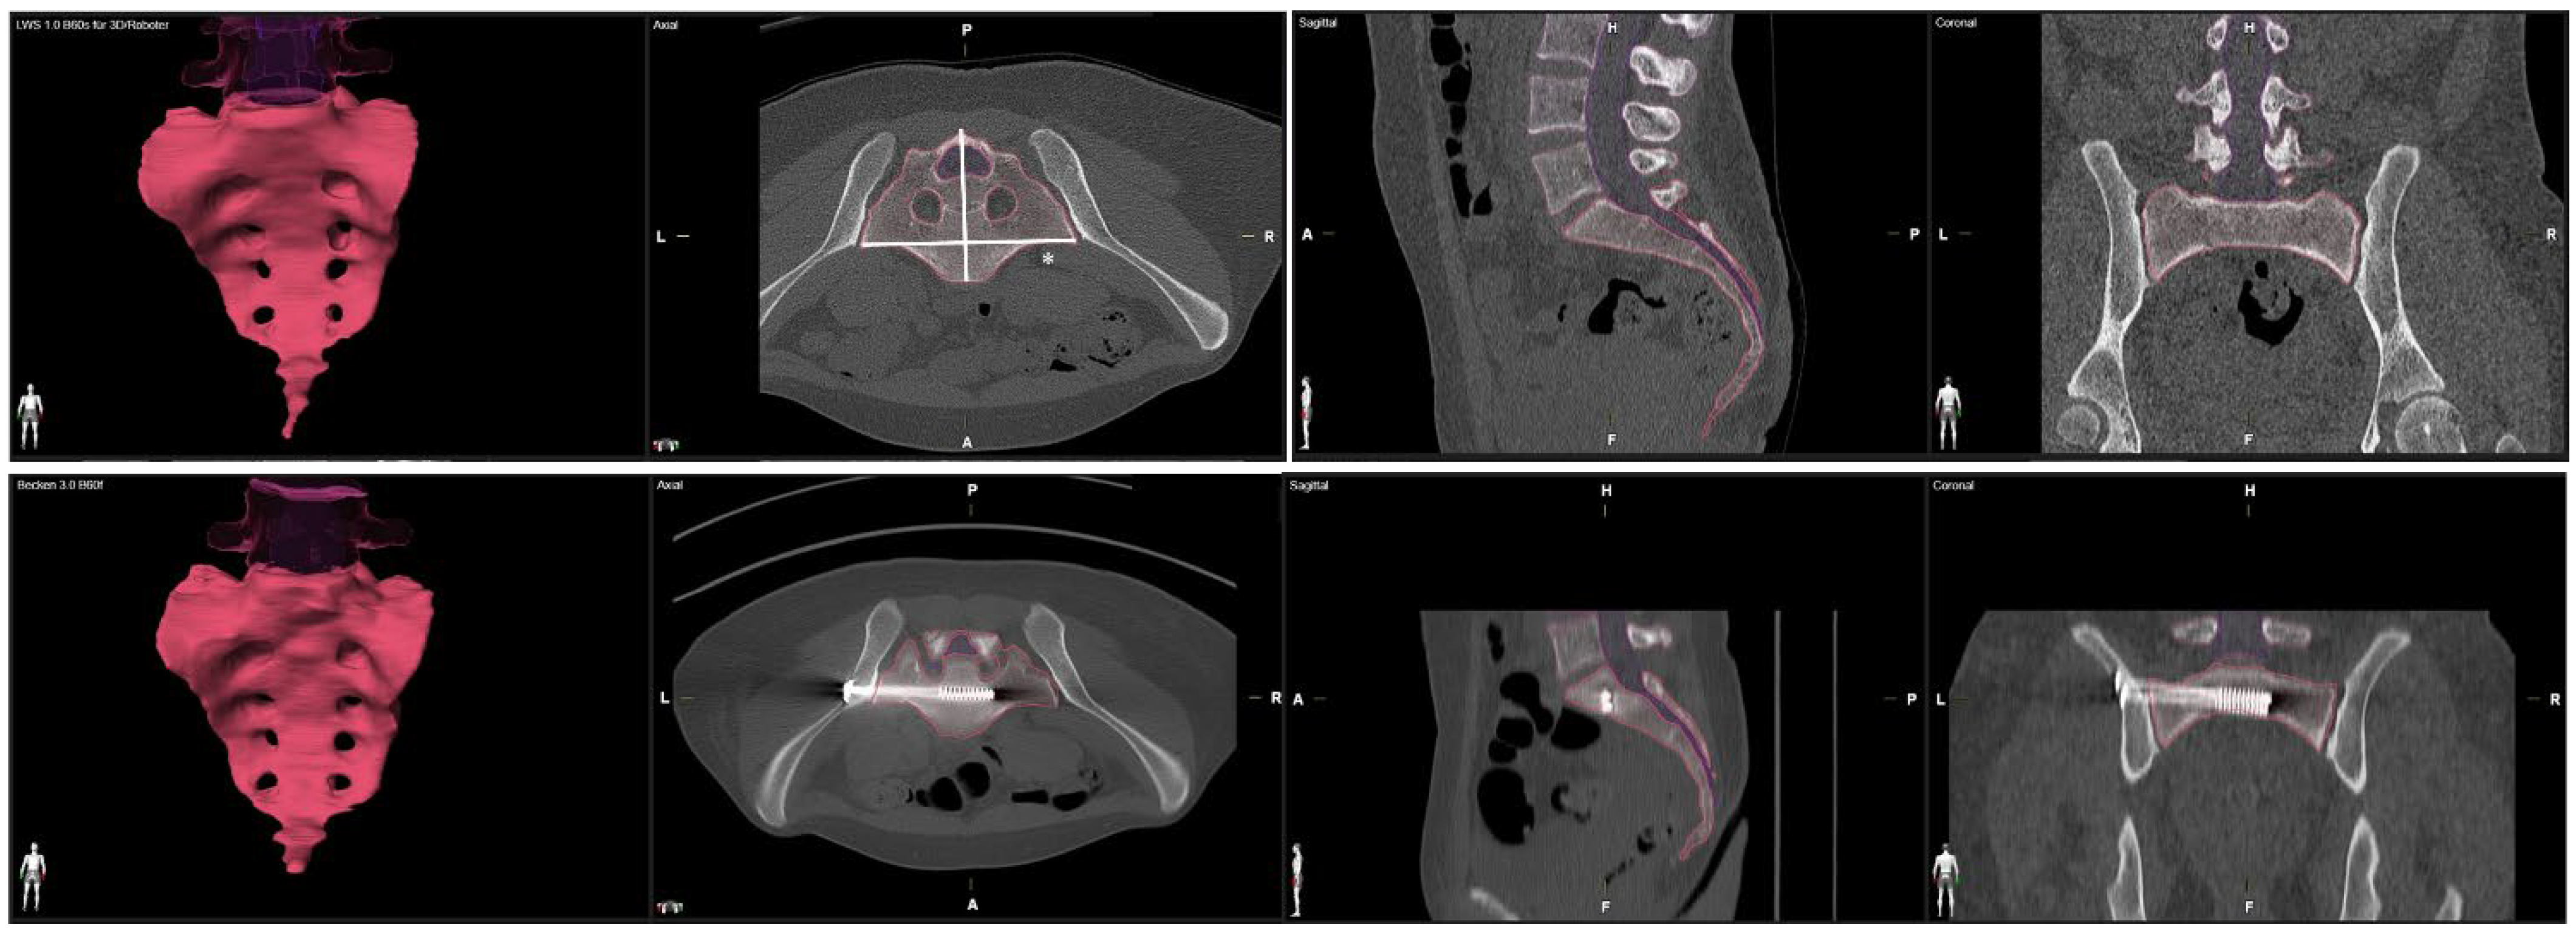

We processed an axial multi-planar bone kernel reconstruction (MPR) based on a preoperative and a postoperative computed tomography with a slice thickness of 1mm. We used the Brainlab Anatomical Mapping Software Package Version 1.1.1.8 of the Brainlab elements Software (Brainlab Inc., Munich, Germany) for volumetric measurement of the sacrum. The anatomical mapping software performs an automatic segmentation of the CT dataset and identifies the boundary of the sacral bone to process the volume of the sacrum. To ensure excellent data quality, we performed a manual post-processing of the automated reconstruction to adjust the exact borders of the sacral bone. We used the automatic volumetric report for calculation of the pre- and postoperative sacral volume (Figure 1). We measured the medio-lateral sacral diameter (MLSD) according to the Response Evaluation Criteria in Solid Tumors (RECIST) as the longest diameter of the sacrum within axial slices [15] (Figure 1).

Figure 1.

Volumetric measurement of the sacrum in preoperative and postoperative CT scans. Medio-lateral sacral diameter (MLSD) according to the Response Evaluation Criteria in Solid Tumors (RECIST) marked by *.